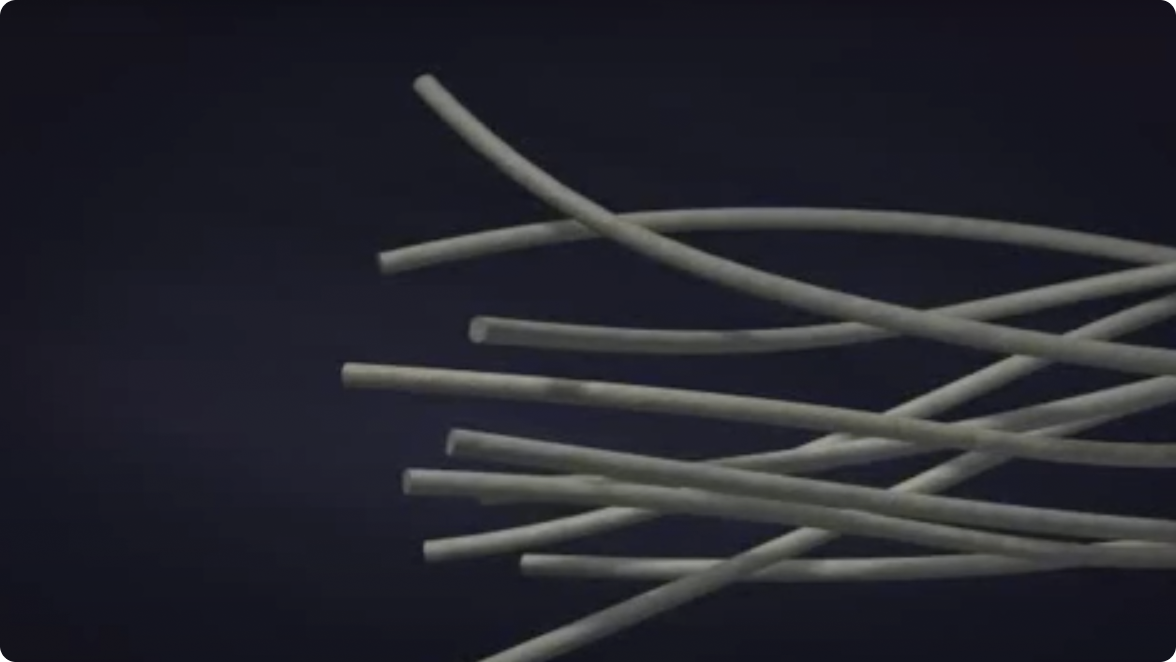

Construcción con tecnología Hydrofiber®

Proceso de producción de la tecnología Hydrofiber®

Apósitos AQUACEL con Hydrofiber®